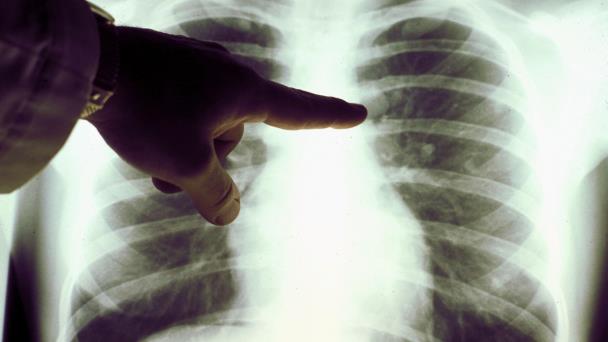

Ciudad de México. - Cerca del 85% de los enfermos de cáncer de pulmón son fumadores y más del 90% de la población conoce los riesgos de fumar, sin embargo, continúan fumando por la incapacidad de abandonar este nocivo hábito, sólo el 7% de los fumadores adultos dejarán el tabaco de manera definitiva, dijo el doctor José Manuel Mier Odriozola, director de la Clínica de Cáncer de Pulmón y Tumores del Tórax, Hospital Ángeles Lomas,

En el marco del Día Mundial Sin Tabaco que se conmemora el 31 de mayo, el Dr. Mier señaló que anualmente 6,123 mexicanos enferman de cáncer de pulmón debido al tabaquismo de los cuales 5, 165 fallecen a causa del humo del cigarrillo que contiene aproximadamente 7 mil sustancias sólidas tóxicas, de las cuales por lo menos 70 son completamente cancerígenas.

Datos de GLOBOCAN del 2020 para el Global Cancer Observatory, registraron más de 2 millones de casos de cáncer de pulmón mundialmente y 1.8 millones de muertes asociadas. En México el cáncer de pulmón tiene una incidencia de 7 mil 811 casos y 6 mil 733 muertes asociadas.